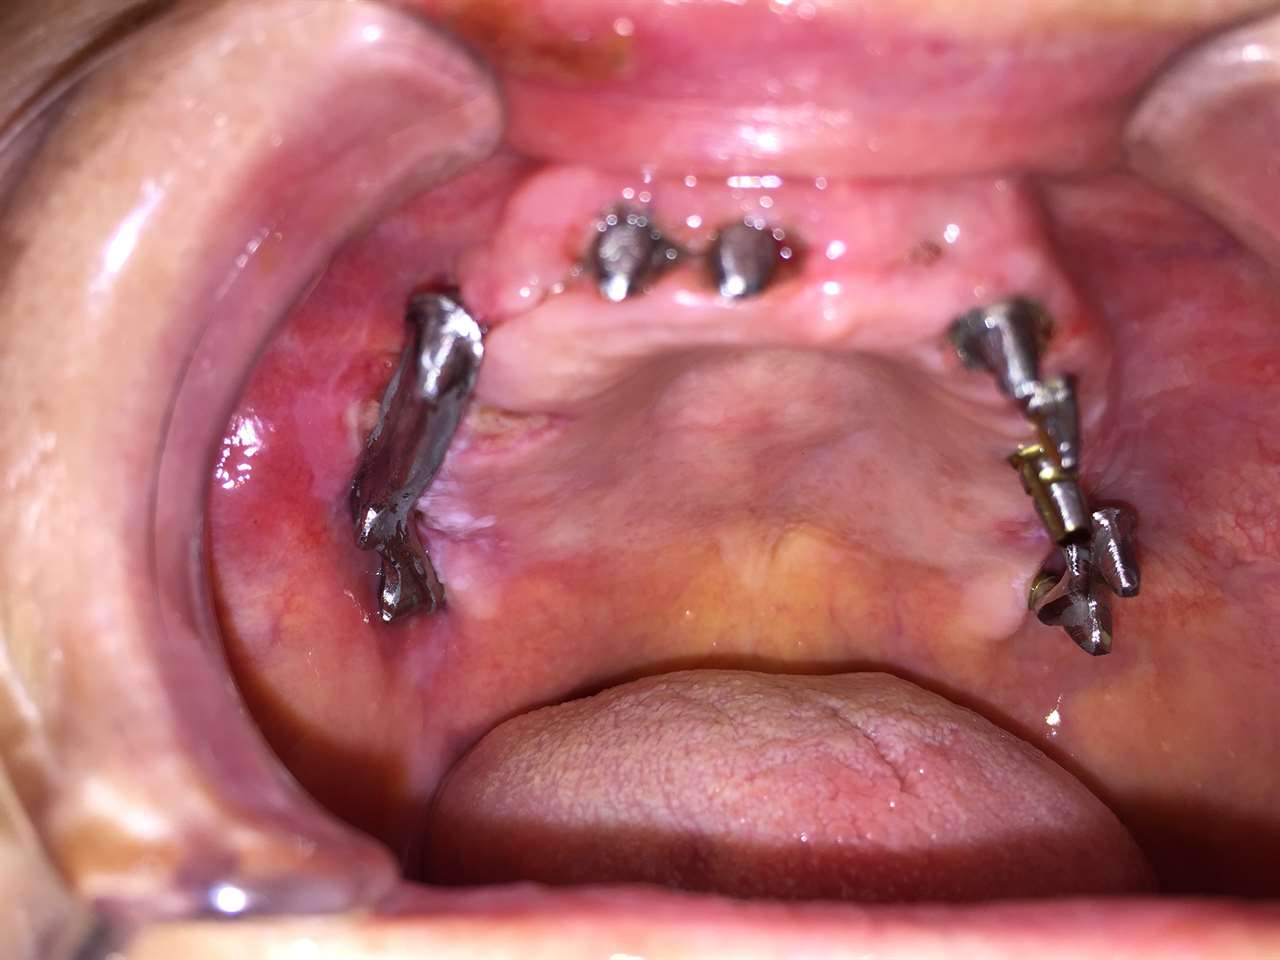

Teljes fogatlanság helyreállítása 2 nap alatt

Teljes fogatlanság helyreállítása 2 nap alatt azonnal terhelhető svájci IHDE implantátumokkal és PMMA műanyag hidakkal. Intraorális szkennerrel vettünk lenyomatot az implantáció után, és erre a digitális mintára készítette el a fogtechnika a hidak digitális tervezését, majd faragta ki műanyagból. Ezt a gyors munkát az azonnal terhelhető implantátumok és a digitális lenyomat, tervezés segítségével tudtuk megcsinálni mindössze 2 nap alatt. Dr. Kelemen Péter és a Symbion Fogtechnika munkája.